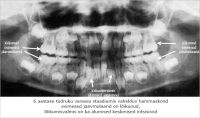

Hammaste röntgenpildid erinevas vanuses

7